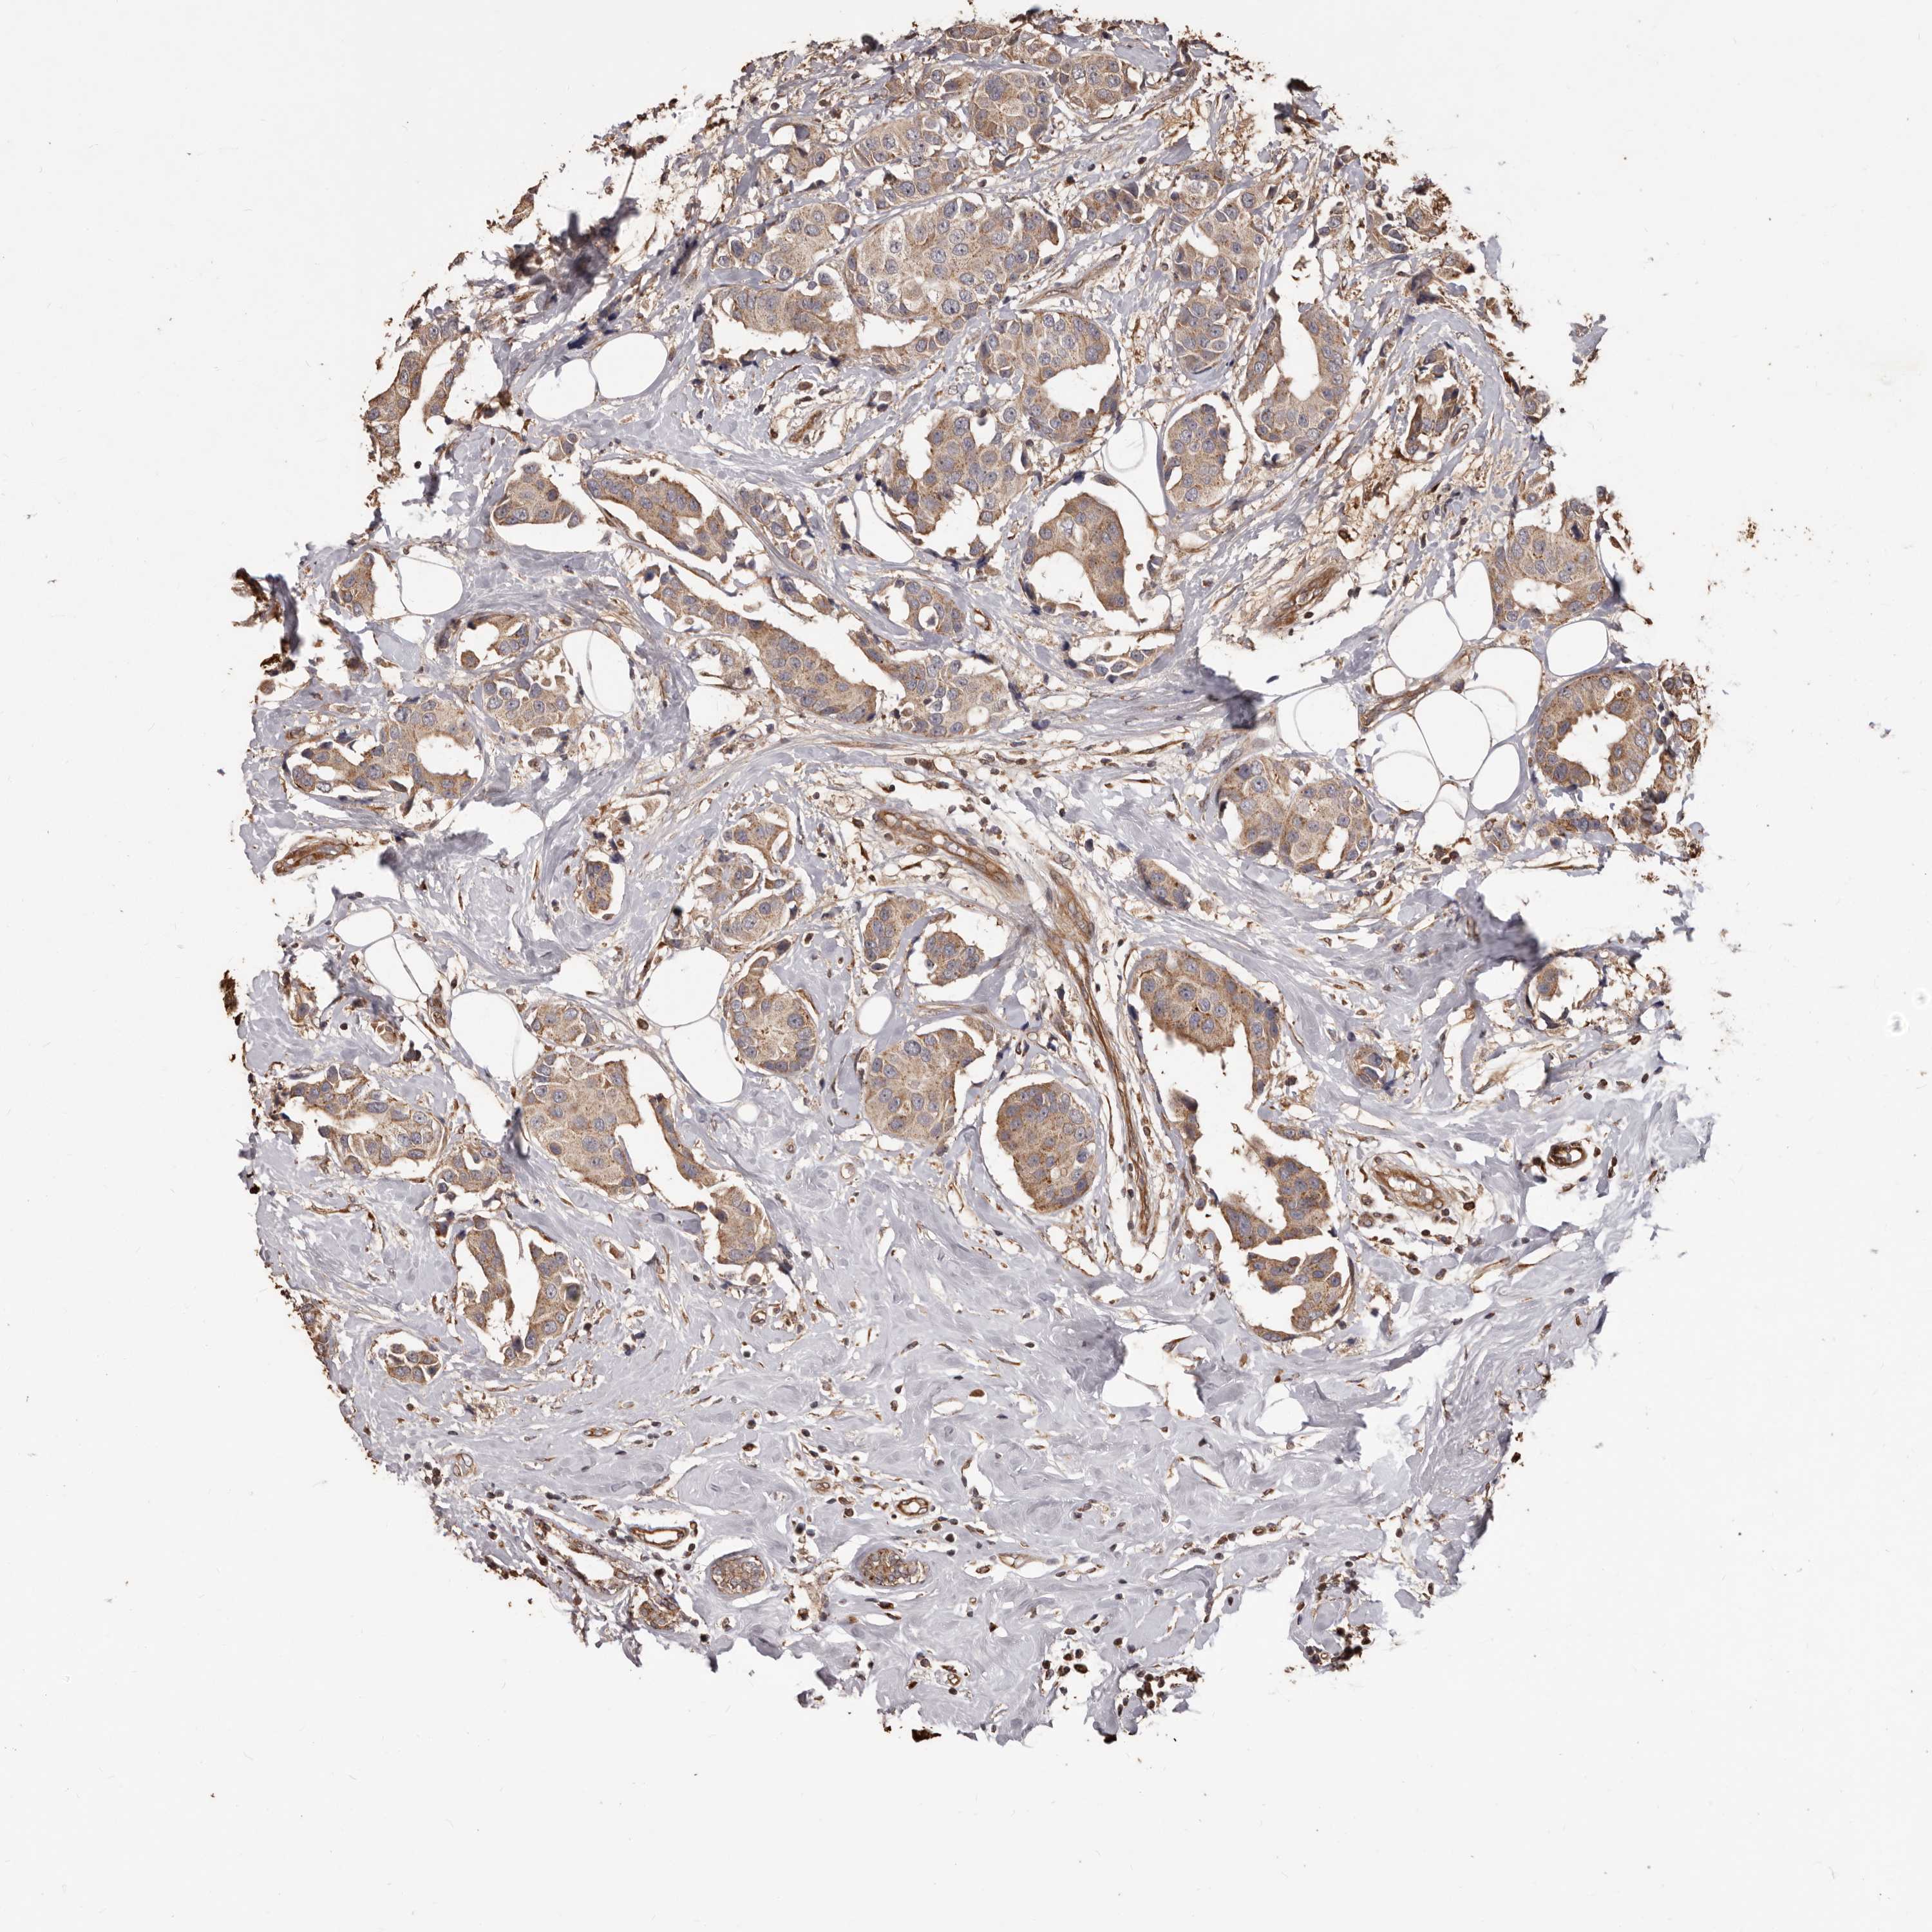

CANCER BREAST CANCER Show tissue menu

BRCA TCGA BRCA VALIDATION PROTEIN EXPRESSION